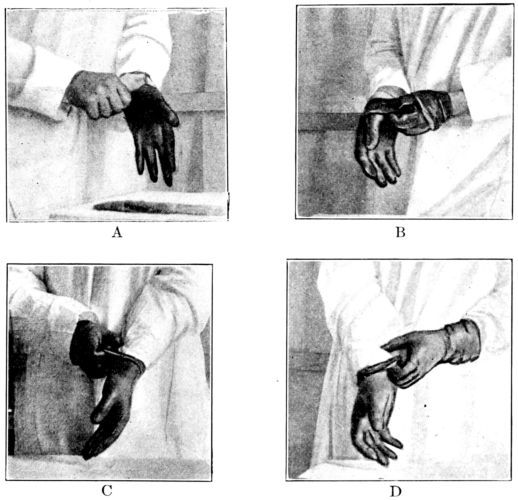

| 78. | Successive steps in proper method of putting on gloves | 255 |